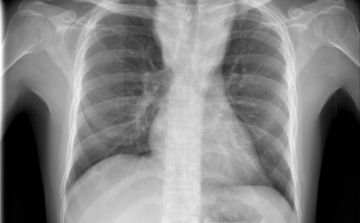

Terjed a tbc Szatymazon?

Hétfő reggel óta tbc-tesztet végeznek el a gyerekeken egy szatymazi általános iskolában, ahol egy hete fertőző tüdőbetegségben halt meg egy korábban ott dolgozó nő - közölték az M1 aktuális csatorna déli Híradójában.